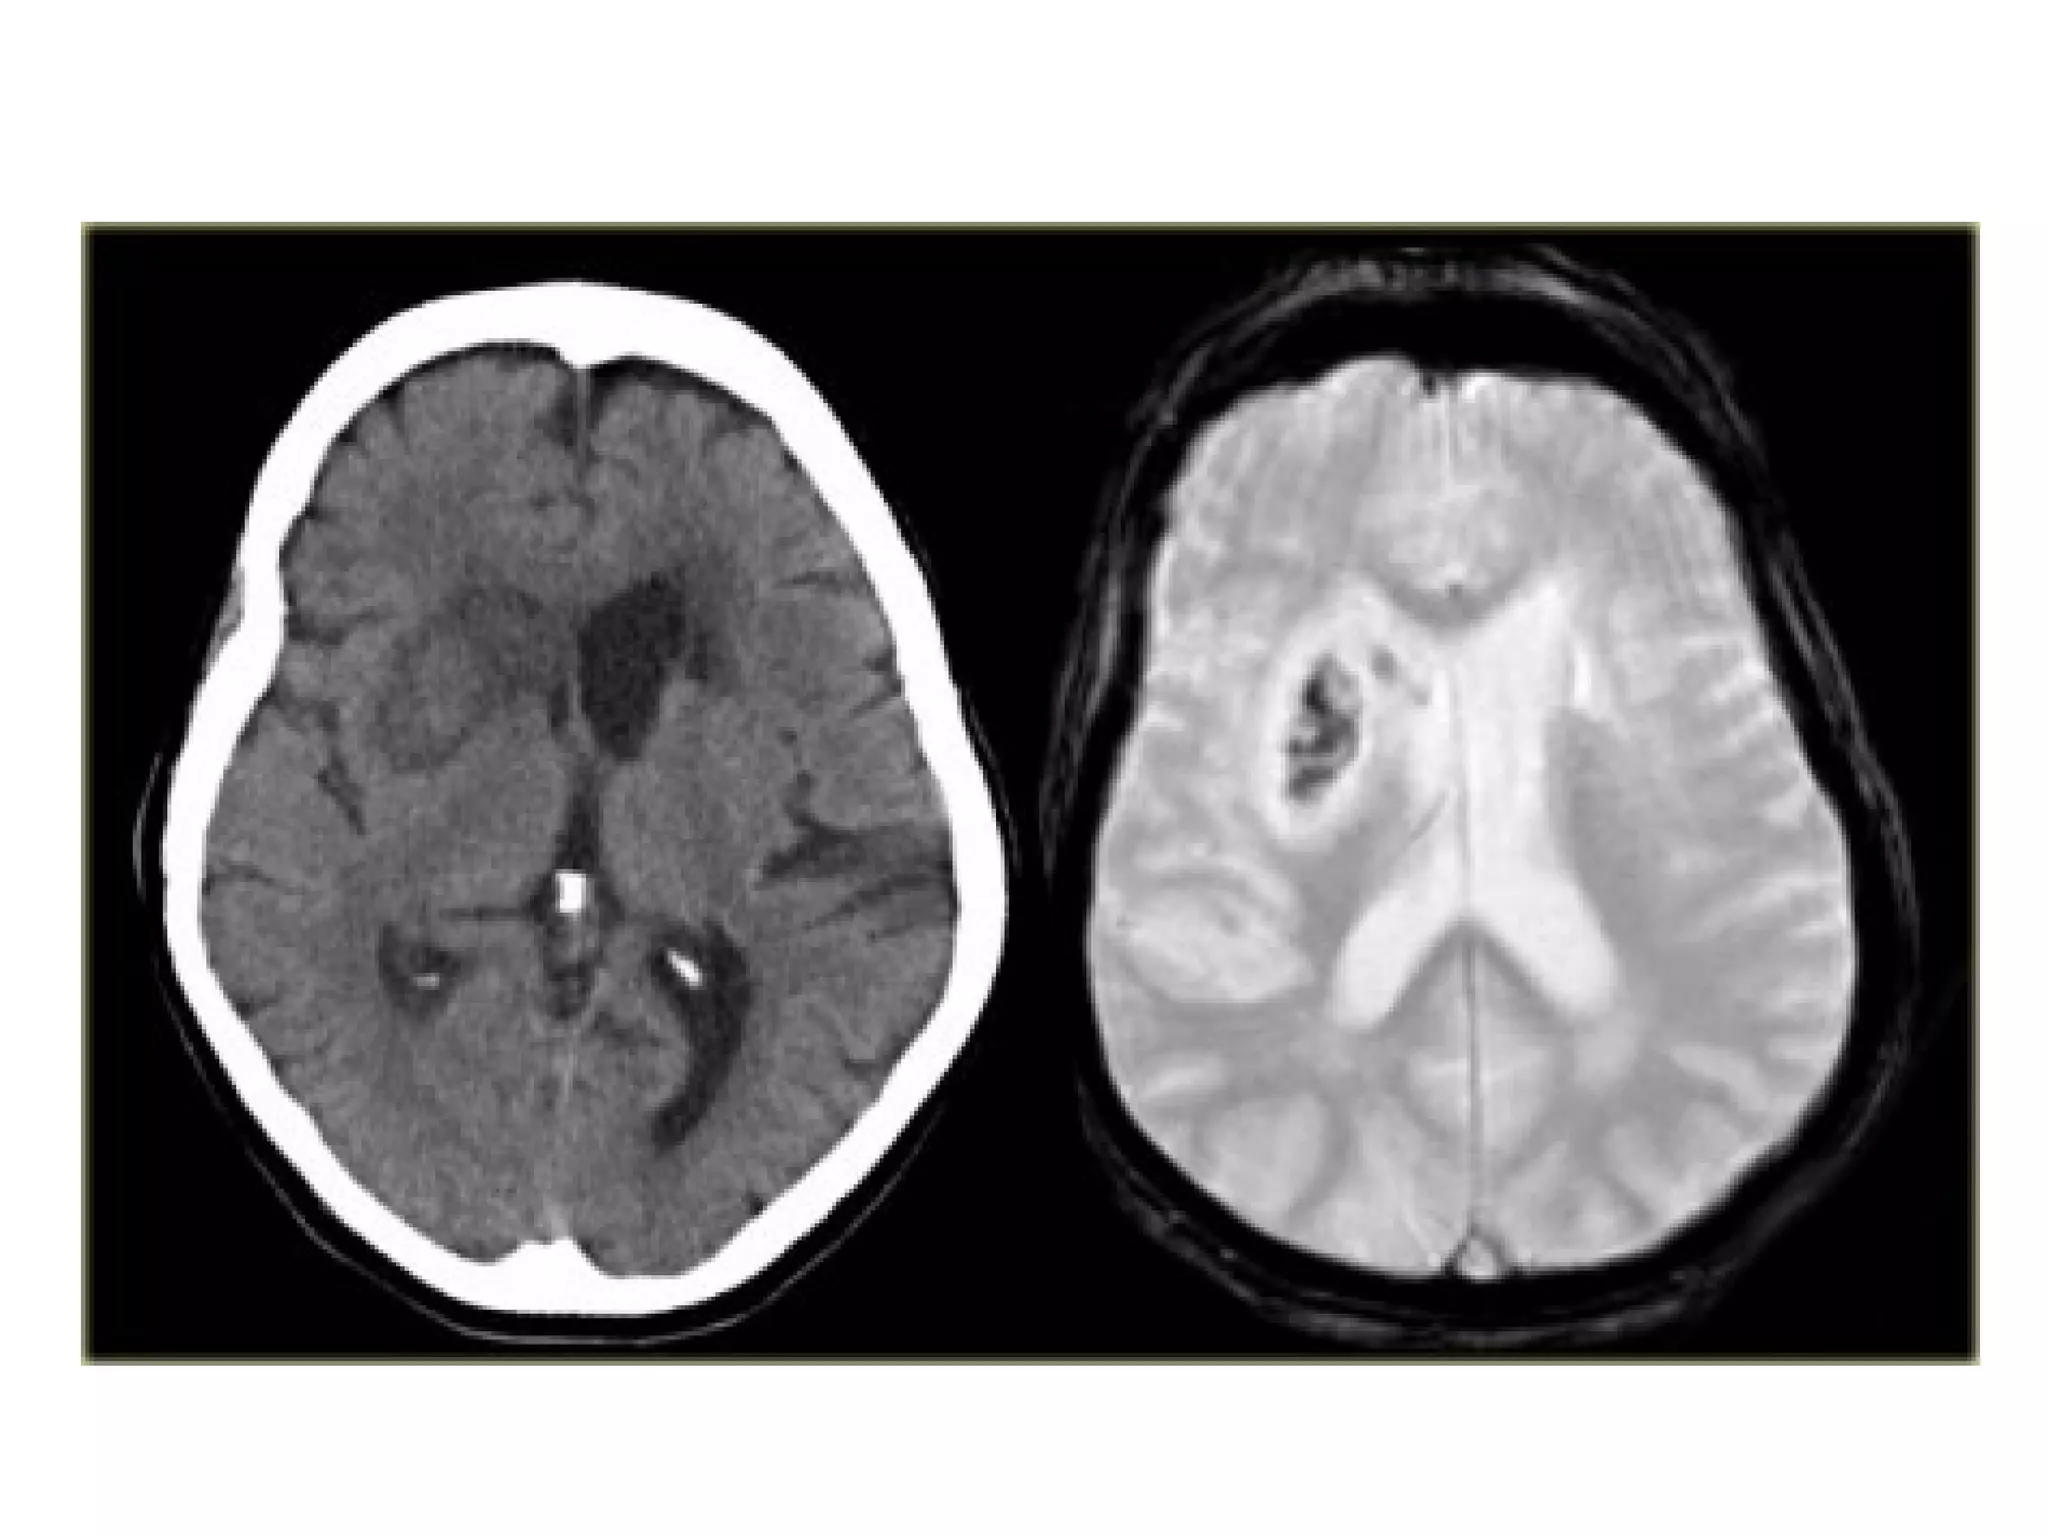

CT , Hemorrhagic evolution of initial ischemic infarction with

significant midline shift